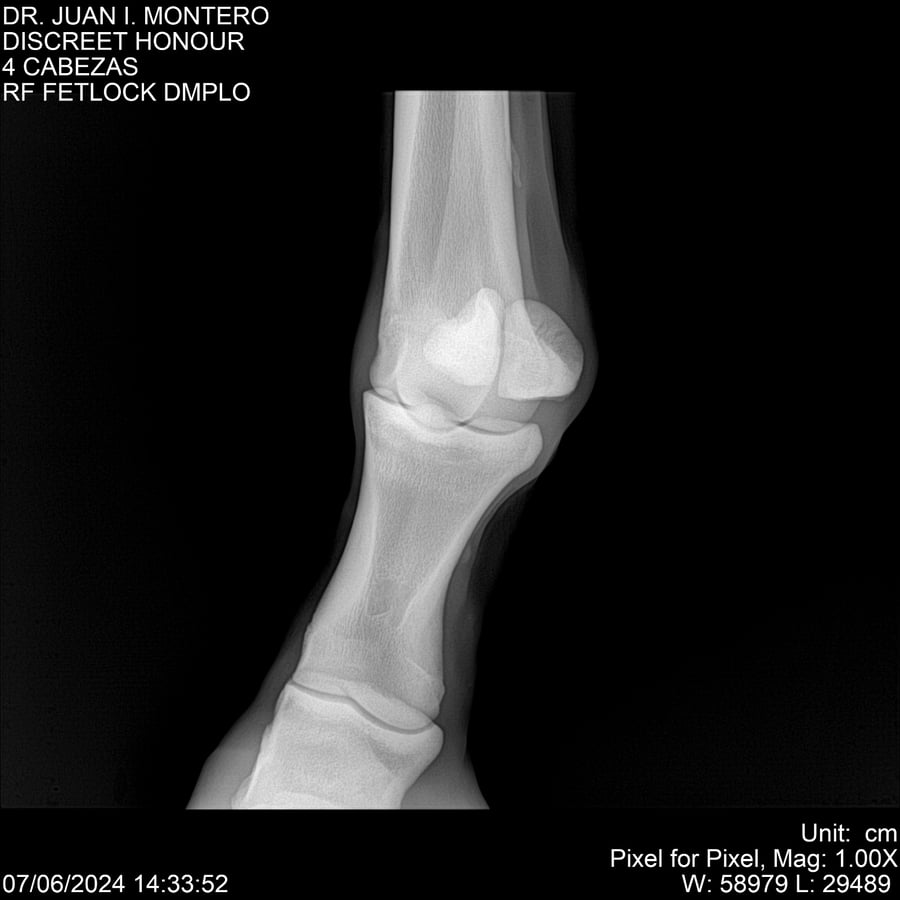

LOTE 6, DISCREET HONOUR 🔥 🔥 🔥 Lote Anterior Volver al remate Lote Siguiente Ficha Contacto Montevideo - Ficha del Lote Identificador: #281093 Categoría: Yeguarizos Montevideo - 82 Visualizaciones ClicData Contacto Empresa: Abelenda N. R., Walter Hugo Nombre*: Teléfono* : E-mail* : Mensaje Enviar Registrese gratis Este contenido Exclusivo está disponible sólo para usuarios registrados Ingresar